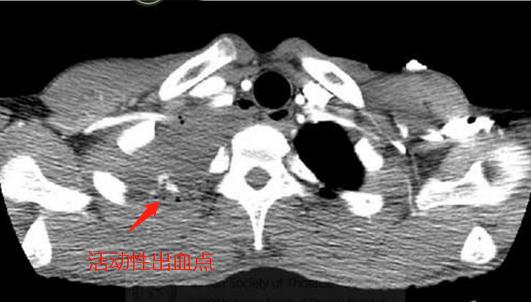

病人生命体征不稳,要警惕失血性休克,先找到出血点,马上急诊增强CT:

增强扫描发现右肺尖背侧造影剂渗漏,符合活动性出血,需要手术!

在电视胸腔镜下,看到了肺尖部多个肺大泡,周围有胸膜黏连带,可见活动性出血点,顺利结扎、引流。